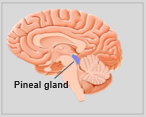

A neuroanatomia é o ramo da anatomia que estuda a anatomia do sistema nervoso, ou seja, a estrutura, a função e a organização do sistema nervoso. O sistema nervoso é um dos sistemas mais complexos do corpo humano e inclui o cérebro, a espinal medula, os nervos periféricos e os gânglios nervosos. A neuroanatomia preocupa-se com a forma como estas estruturas estão ligadas entre si, como os sinais são transmitidos entre as células nervosas e como as diferentes partes do sistema nervoso trabalham em conjunto para controlar as funções corporais e cognitivas. Os neuroanatomistas utilizam técnicas de imagiologia avançadas, como a ressonância magnética (MRI), a tomografia por emissão de positrões (PET) e a microscopia para visualizar as estruturas e funções do sistema nervoso.